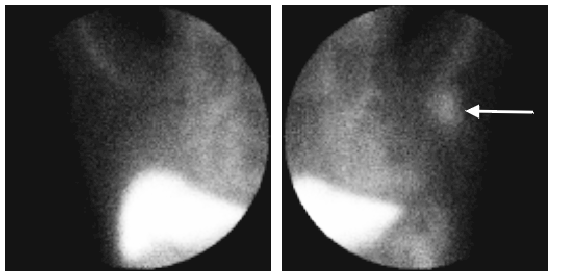

99mTc-MAb-170 has been used successfully in identifying metastatic breast adenocarcinoma in various lymph node groups. Metastatic disease can be visualised in the left axillary lymph nodes and corresponds to known disease at this site.

Figure 4: Planar image of the uptake of 99mTc-MAb-170H.82 in the left axilla at 24 hours post injection.